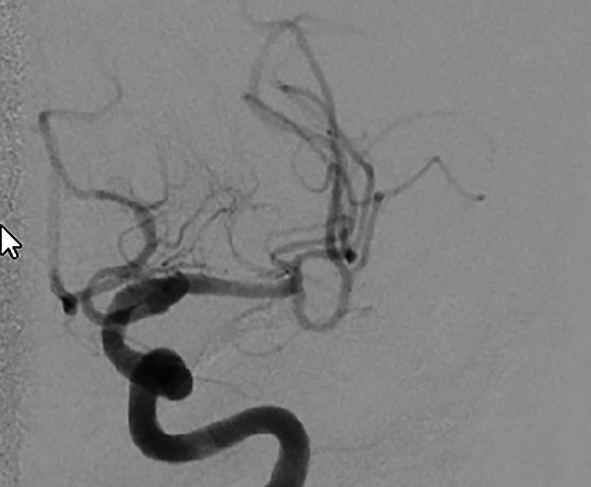

b) Wiedereröffnetes Gefäß nach Thrombektomie in Solumbra-Technik

Der Einsatz eines Stentretrievers ist die bisher am häufigsten eingesetzte Technik. Hierbei handelt es sich letztlich um einen modifizierten intrakraniellen Stent, der an einem 0,014-inch-Draht befestigt ist. Der Thrombus wird mit einem 0,014-inch-Mikrodraht und einem 0,021-inch-Mikrokatheter passiert. Über den Mikrokatheter wird der Stentretriever im Thrombus freigesetzt, der Blutfluss nach distal ist jetzt wiederhergestellt. Nach einer Wartezeit von 5–8 Minuten, in der sich der Thrombus in den Stentmaschen festsetzen soll, wird der Stentretriever entfaltet zurückgezogen. Damit der Stentretriever ohne Abscheren des Thrombus in der langen Schleuse geborgen werden kann, muss eine Schleuse mit abschraubbarem Ventil verwendet werden. Bei der Adapt-Technik (direct aspiration first-pass thrombectomy) wird ein großlumiger Aspirationskatheter direkt vor den Thrombus gebracht, bei einem Verschluss der proximalen A. cerebri media wird dazu ein 6F-Katheter verwendet. Über eine Aspirationspumpe wird dann der Thrombus in den Katheter gesaugt. Nach frühestens 90 s wird, falls der Thrombus nicht komplett aspiriert werden kann, der Aspirationskatheter unter Sog mit dem Thrombus an der Katheterspitze zurückgezogen. Bei der Solumbra-Technik, benannt nach ihrem Erstbeschreiber, wird ein Stentretriever-Manöver mit einem Aspirationskatheter, der bis an den Thrombus herangeführt wird, kombiniert. Eine Weiterentwicklung der Solumbra-Technik ist die SAVE-Technik (stent retriever assisted vacuum-locked extraction). Der Stentretriever wird zu 2/3-Dritteln distal des Thrombus freigesetzt. Hierdurch wird ebenso wie durch das Rückholen in einen Aspirationskatheter das Risiko einer distalen Embolisation verringert.

Durch die Verwendung eines Ballon-Führungskatheters, der beim Rückzug des Thrombusmaterials in der ACI geblockt wird, kann eine Flussumkehr erreicht werden. Auch diese Technik dient der Vermeidung von Embolien nach distal oder in andere Gefäßterritorien.